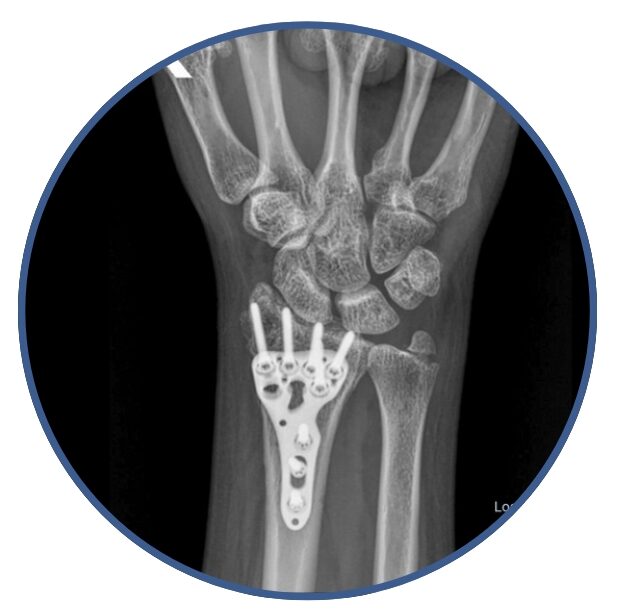

Traumatología y Ortopedia General

Manejo de patologías del sistema músculo-esquelético del Adulto, Artrosis, Fracturas, Etc.